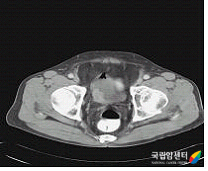

[ 근침윤성 방광암의 전산화단층촬영 사진 ]

전산화단층촬영은 방광암의 유무, 위치 등을 확인할 수 있으며, 근침윤성 방광암에서 암이 방광벽을 뚫고 주위 조직으로 어느 정도 퍼져 나갔는지 범위를 평가하고 림프절 비대 및 다른 기관으로의 전이 등을 평가하는데 도움을 줍니다.